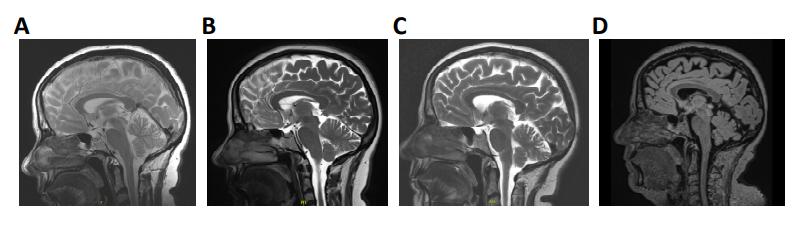

Supplementary Figure 1. Mid-sagittal T1/T2 and Flair-sequence MR images. Images were taken in

(A) 2010, (B) 2014, (C) 2019, and (D) 2024, respectively. |